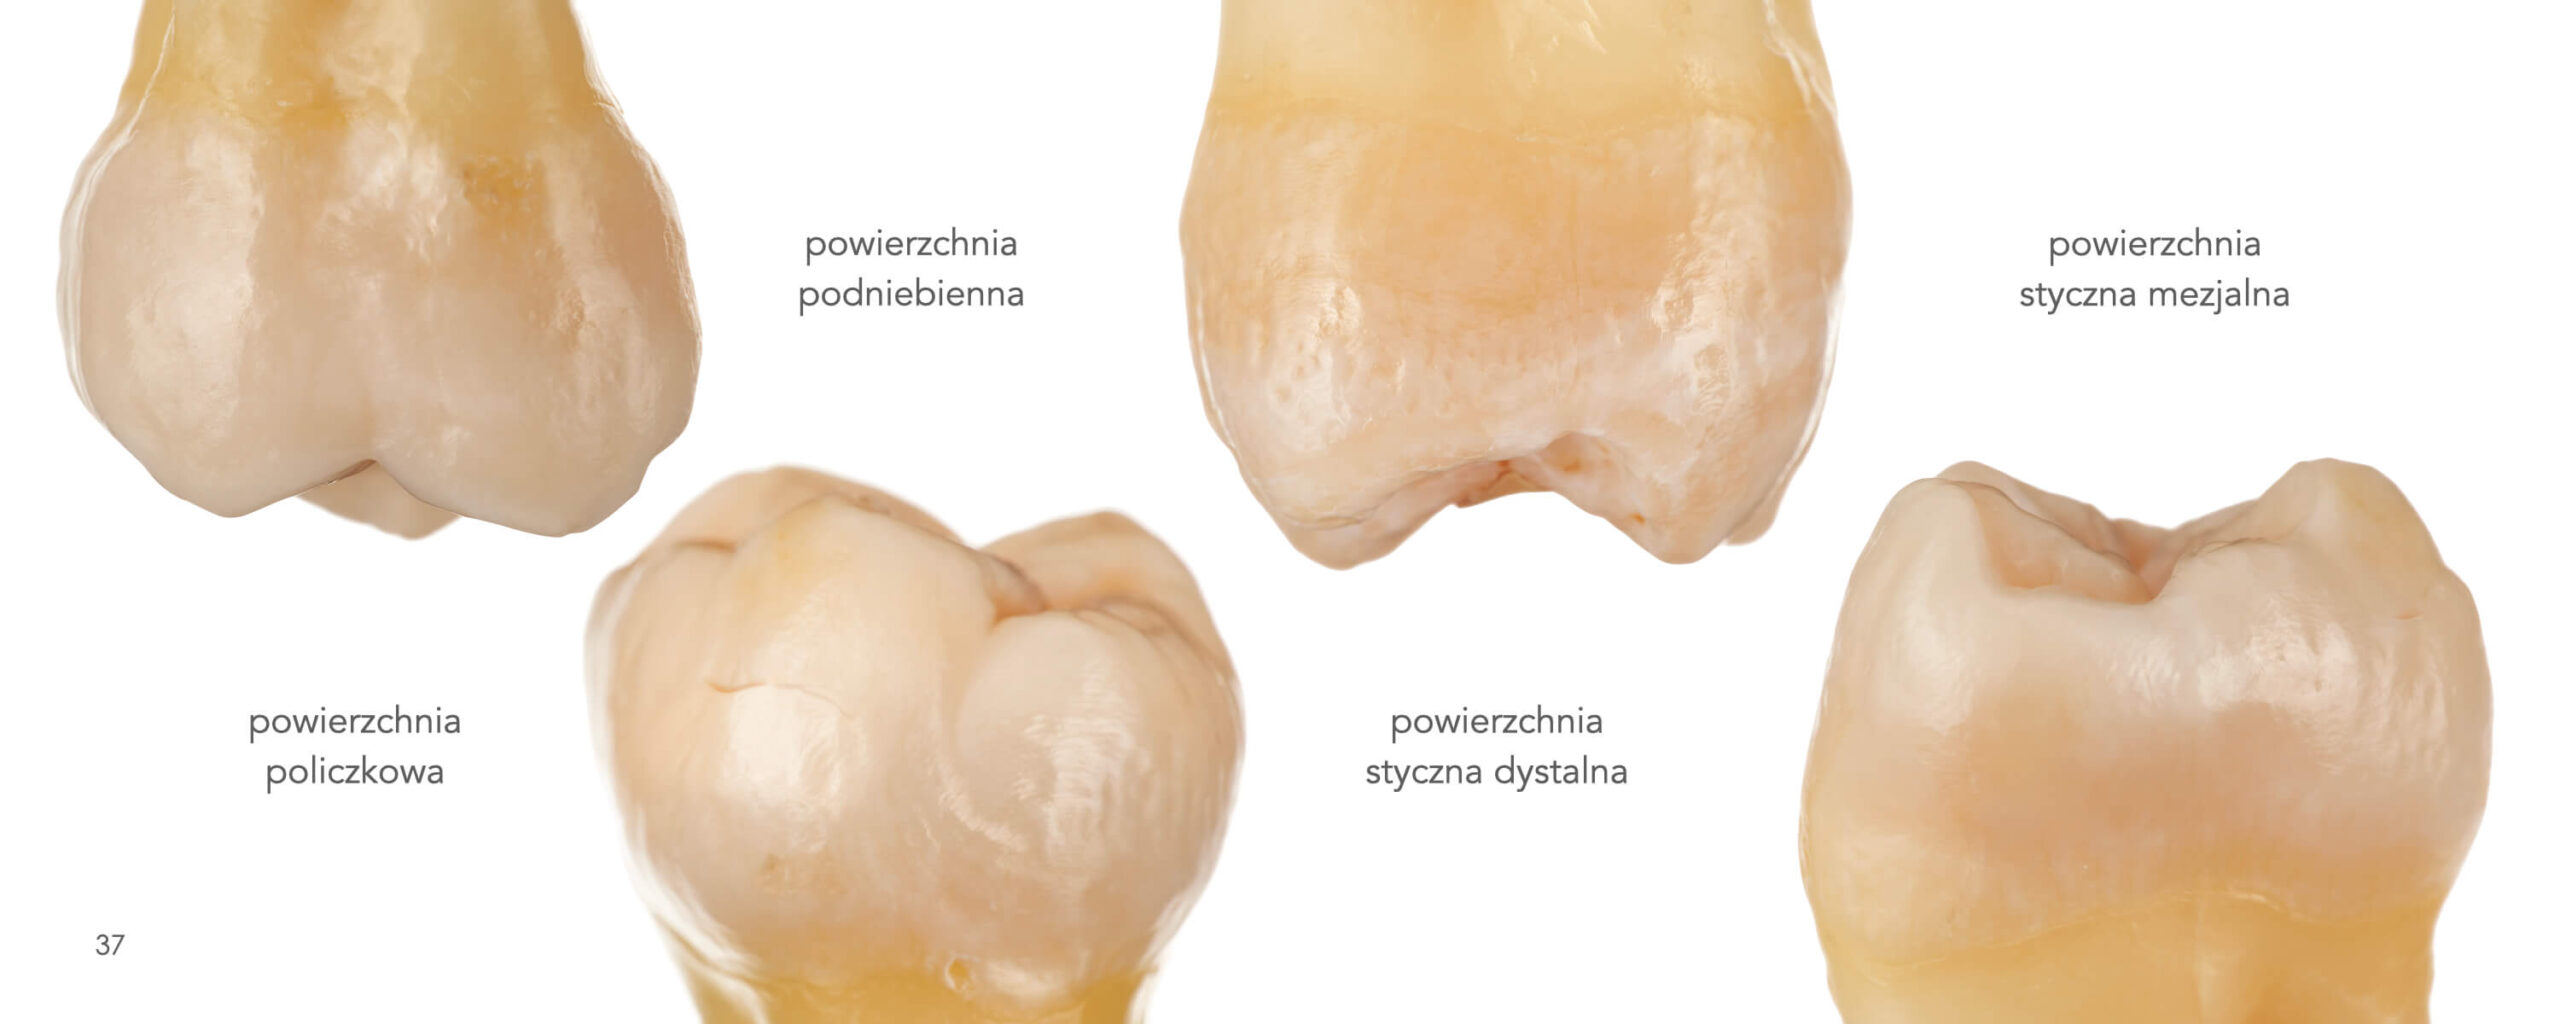

Posterior Teeth Morphology

Direct Composite Restorations

What does the anatomy of natural teeth look like?

Does the shape of the cusps matter?

How to characterize the occlusal surface to emphasize the

natural effect?

You’ll find the answers to this and more. After reading this atlas, you will be prepared how to create the biomimetic